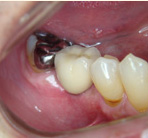

インプラント

第3の歯インプラントも診断が一番大切。適切な治療が成功の鍵です。

入れ歯から開放されて快適な食生活を送って下さい。残っている歯にとっても最適な治療法です。

- 施術前

- 施術後

- イメージ